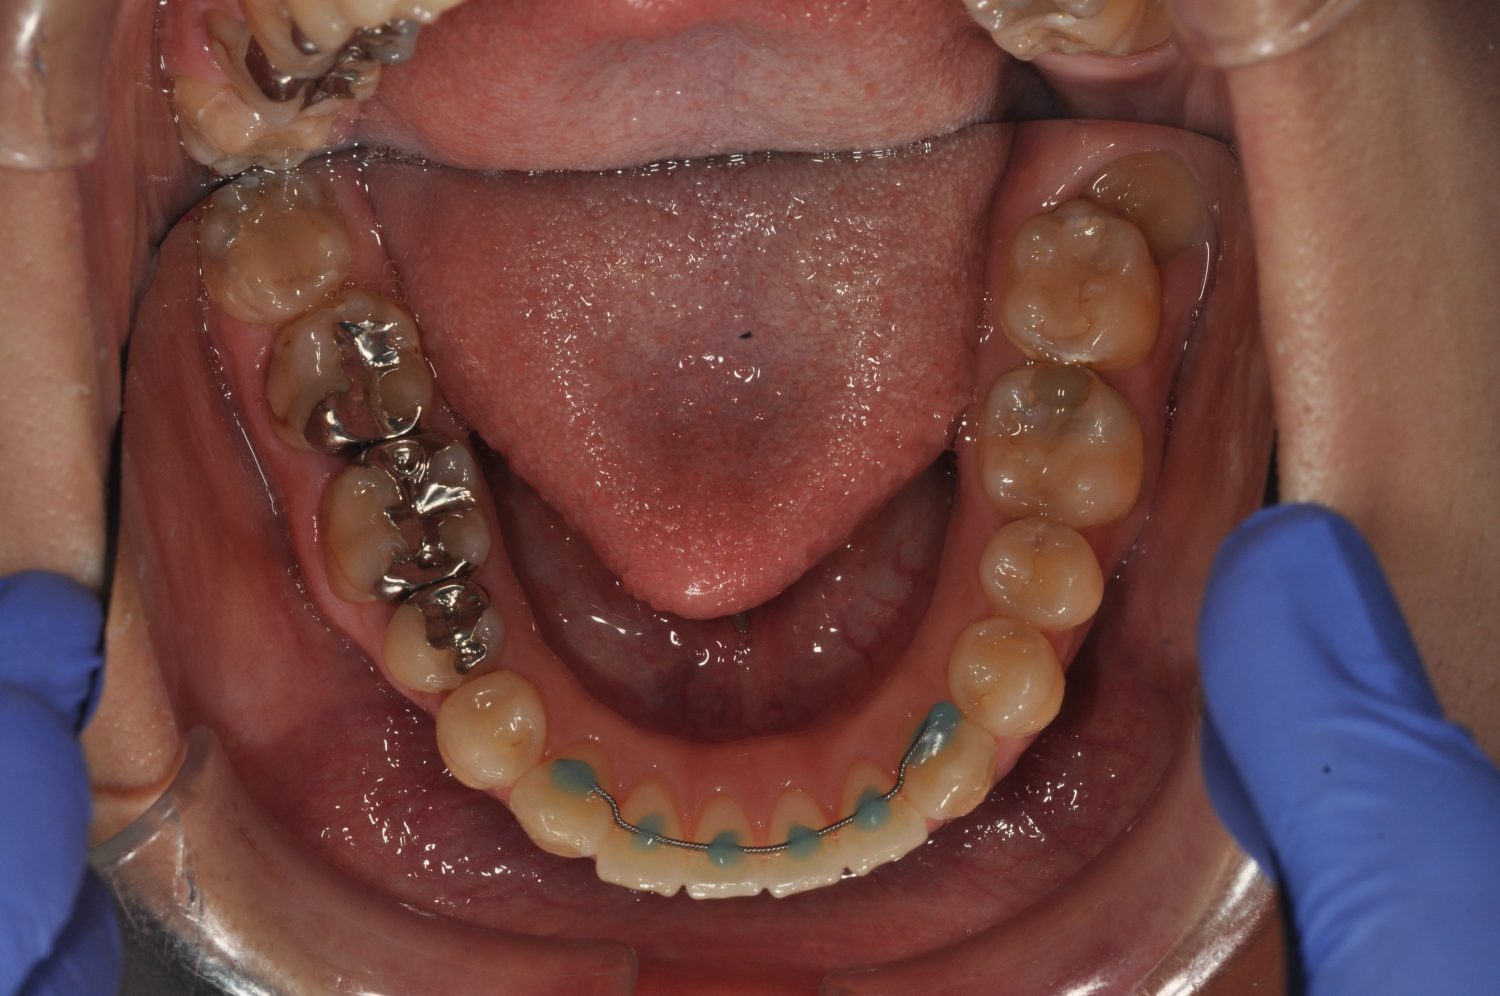

| 主訴 | 前歯の出っ歯を直したい |

| 治療内容 | 上下顎とも標準範囲であるが、上下顎前歯ともに唇側傾斜による、上下顎前突。上顎小臼歯を抜去し配列を行うこととした。 |

| 想定されたリスク | 矯正器具の装着に伴い、むし歯や歯周病のリスクがありました。また、歯根吸収や歯肉退縮のリスクもありました。 |

上下顎前歯の唇側傾斜による上下顎前突。オーバージェットが大きいため、上顎のみの抜歯で配列を行った。